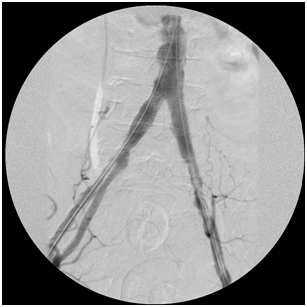

The images below illustrate such a problem. This patient in addition to having irregular chunks of calcium narrow his aorta has significant narrowing of the origins of his common iliac arteries (ostial stenosis), which along with the narrowings above and below them diminished the amount of blood reaching the patient’s feet from the aorta, causing symptoms.

By simultaneously deploying a stent across each common iliac ostial narrowing, I corrected the problem, delivering more blood into the patient’s feet. The first image shows the narrowings before the stents were deployed; the second image displays the process of stent deployment; the third image was taken after I landed the stents.